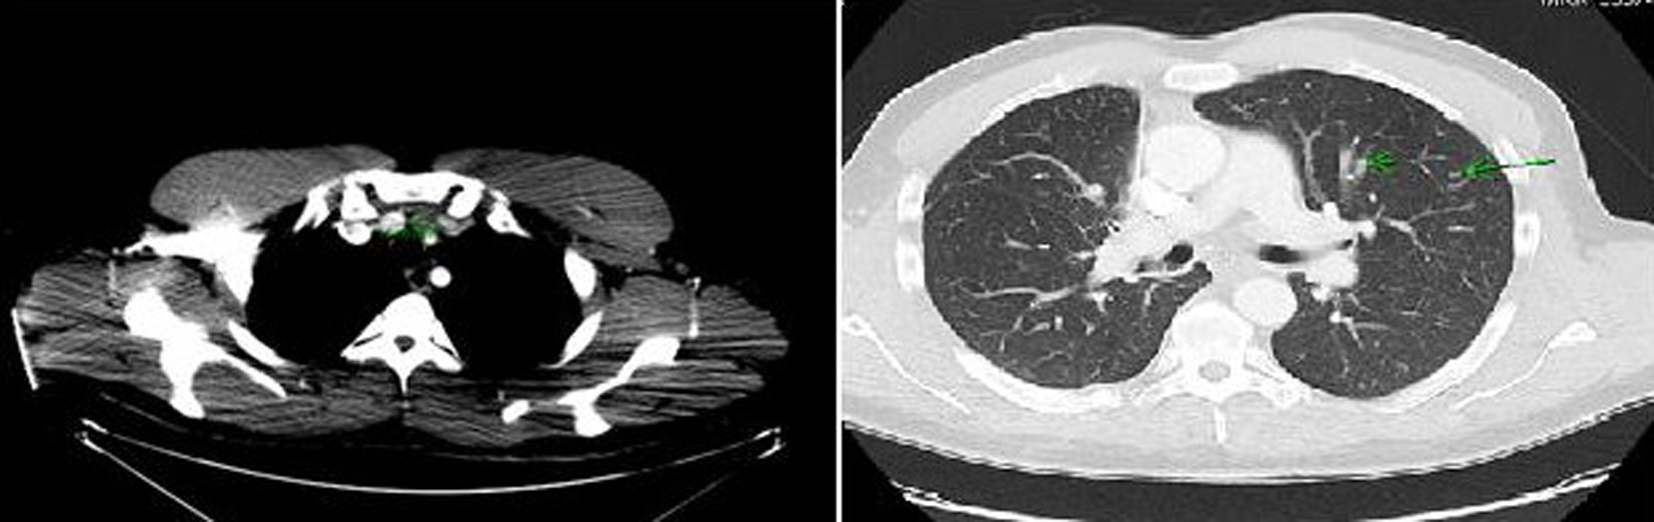

Computer tomography (CT) of the neck and chest confirmed a heterogeneous enhancing mass measuring 2.5 × 1.3 × 3.8 cm arising from the isthmus of the thyroid gland, extensive multiple bilateral lymphadenopathy in the neck and superior mediastinum, and multiple pulmonary nodules in both lung fields (Fig. 2).

![]() Click for large image | Figure 2. Computer tomography of the neck and chest showing a mass arising in the isthmus of thyroid gland and multiple pulmonary nodules in both lung fields. |